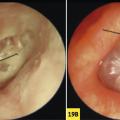

Aspects faisant suspecter un cholestéatome

OTALGIE

OTITE